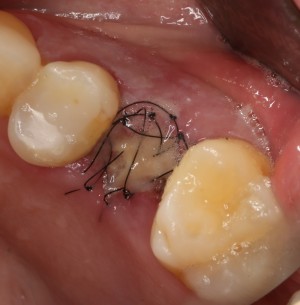

В этом случае мы используем Mucograft Seal как наименее травматичный и наиболее простой способ герметизации лунки:

Матрица подшивается узловыми швами к краям лунки, таким образом достигается ее герметичность:

И вот что важно про швы. Любые другие способы подшивания что матрицы, что десневого лоскута, например П-образные или Х-образные швы, во-первых, не обеспечивают нужной герметичности, а во вторых создают излишнее натяжение краев слизистой оболочки, что приводит их деградации и стимулирует атрофию тканей. Так что лучше потратить побольше времени и зашить лунку так, как надо, чем потом переживать за результат операции.

В принципе, с наложением швов операция заканчивается. По времени такая работа занимает, примерно, полчаса, иногда дольше (40-50 минут), если удаление зуба затягивается.